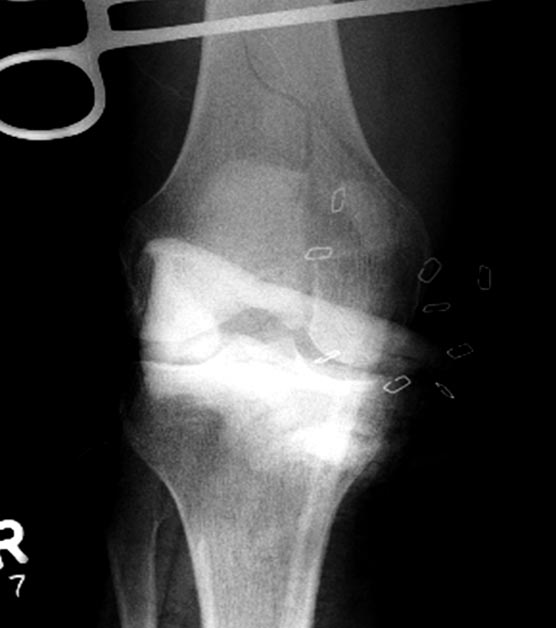

Раны в области коленного сустава и на плече до сих пор чистые, остаются

открытыми. Отсутствует признаки инфекции, решили превратить недостаток в

преимущество, т.е. фиксировать через открытые раны пластинами.

На 9й день фиксация дистального бедра, где фрагмент Hoffa и вертикальный

перелом надколенника, зафиксированы винтами.